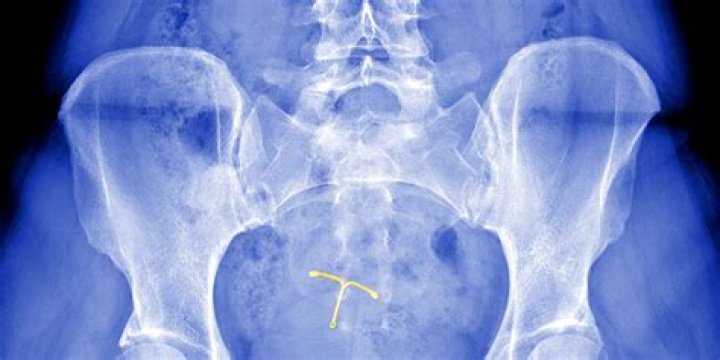

Can Mirena make you crazy?

However, the synthetic progestin hormone that the IUD emits, levonorgestrel, may cause mood swings and other mental health changes for some women. Some women have reported being concerned about anxiety or depression as a side effect of their IUD.

Can the Mirena IUD cause depression? Some people experience mood changes while using hormonal contraception. Data suggest that around 6.4% of people who use the Mirena IUD experience low mood or depression within 5 years.

That also goes for Mirena, the implant, the mini pill, and other progestin-only contraceptives. Some studies found that women using Mirena were more likely to show signs of depression. But other research has concluded that there is no connection.

Mirena lawsuits accuse Bayer Pharmaceuticals of hiding side effects and making a defective intrauterine uterine device (IUD). Women blame the birth control device for organ perforation, dislodging from the uterus and causing pressure buildup in the skull.